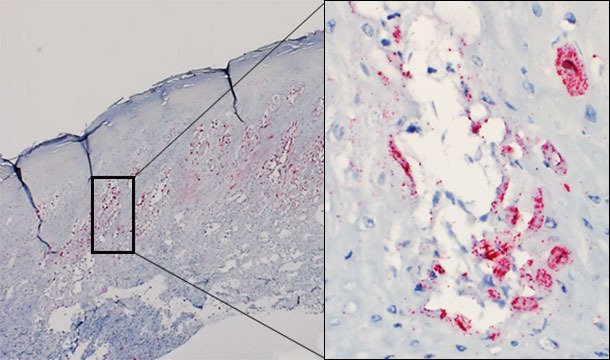

Pese a varios intentos, todavía no se ha podido reproducir experimentalmente la enfermedad vesicular a partir de SVA. Sin embargo, el virus ha sido demostrado mediante hibridación in situ en las lesiones vesiculares de los animales afectados (figura 1). Actualmente se está llevando a cabo un estudio para intentar reproducir la enfermedad vesicular con un SVA recién aislado en el medio-oeste de EE.UU., procedente de cerdos con enfermedad vesicular idiopática.

Figura 1 – Biopsia cutánea de una vesícula de un cerdo afectado. Se detecta la presencia de virus predominantemente en el estrato espinoso de la epidermis. Vesícula intraepidérmica: virus replicándose en los queratinocitos.